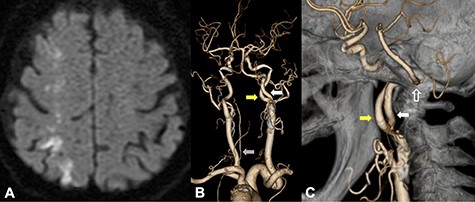

An 87-year-old female presented left homonymous hemianopsia and hemiparesis. She had a past medical history of hypertension and dyslipidemia. Diffusion-weighted imaging (DWI) in magnetic resonance imaging (MRI) showed infarction suggestive of high signal intensity lesions at the border zones between the anterior and middle and the middle and posterior cerebral artery territories (Fig. 1A). It also showed multiple infarctions in the territory of the posterior circulation. Computed tomography angiography (CTA) revealed severe stenosis, which nearly occluded the ICA bifurcation just proximal to the right ICA–PPHA bifurcation. The ipsilateral vertebral artery was absent, and the contralateral VA was rudimentary (Fig. 1B). PPHA originated from the posterior wall of the ICA at the C1–C2 intervertebral space and passed the hypoglossal canal (Fig. 1C). The basilar artery was supplied only by PPHA, and the anterior communicating artery and posterior communicating arteries were absent. CEA was planned to prevent further cerebral infarctions.

DWI on MRI showed infarction suggestive of high signal intensity lesions at the border zones between the anterior and middle and the middle and posterior cerebral artery territories (A); CTA from a posterior view revealed that PPHA (white arrow) originated from the posterior wall of the ICA (yellow arrow); the ipsilateral vertebral artery was absent, and the contralateral VA was rudimentary (B, gray arrow); CTA from a medial view revealed that PPHA entered the cranium through the hypoglossal canal (C, white line arrow).